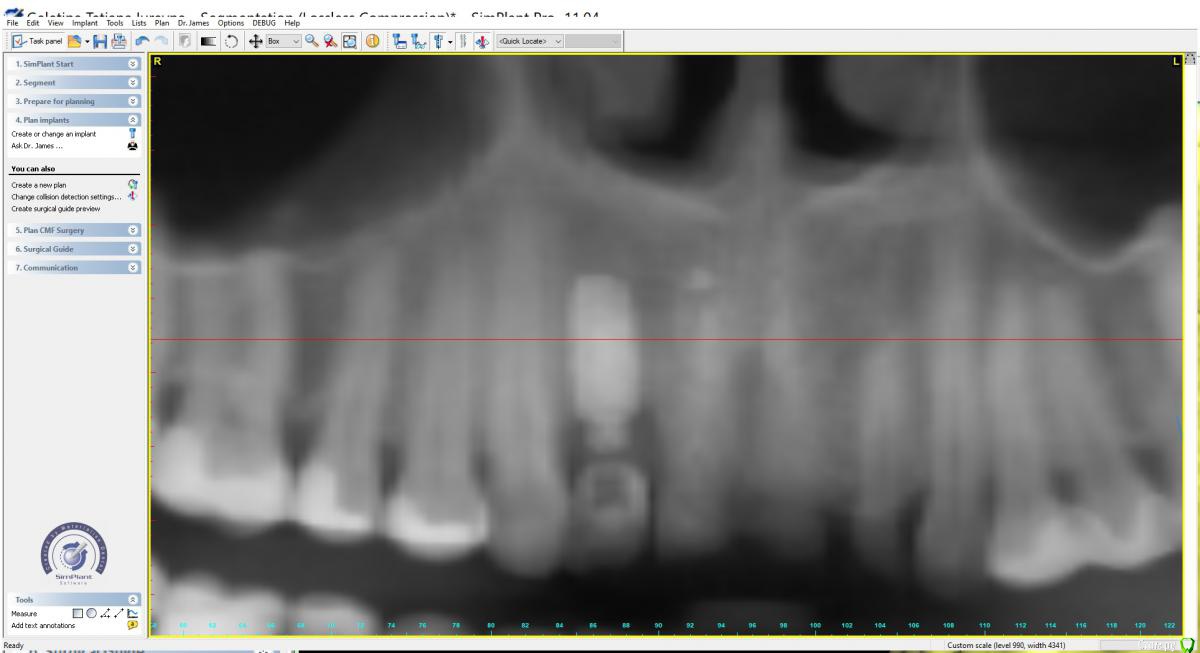

Irouil Опубликовано 1 сентября, 2019 Поделиться Опубликовано 1 сентября, 2019 Тут бы рентген смотреть Ссылка на комментарий

x4ex Опубликовано 1 сентября, 2019 Автор Поделиться Опубликовано 1 сентября, 2019 Тут бы рентген смотреть Ссылка на комментарий

Дмитрий М Опубликовано 3 сентября, 2019 Поделиться Опубликовано 3 сентября, 2019 12 - имплантат.так по снимку 12 - свой зуб! это резорбция у шейки или недозаглубили? Ссылка на комментарий

Dman Опубликовано 4 сентября, 2019 Поделиться Опубликовано 4 сентября, 2019 так по снимку 12 - свой зуб! 358.jpg это резорбция у шейки или недозаглубили? по всем снимкам 12- имплант, вы точно врач? опишите пожалуйста, каким именно? ну видно же, что на примерке ишемия, значит абатмент выталкивает мягкие ткани вестибулярно и коронально. Если делать пластику то трансплантат будет находиться и расти в том же направлении. Значит нужно сделать более вогнутый абатмент с переходом в коронку намного ниже, там, куда мы хотим сместить зенит. а для чего глушить? чтобы получить больше мягких тканей, потом сместить их вестибулярно, и получить необходимую высоту. Также будет возможность провести на раскрытии еще пластику и добавить ещею 1 Ссылка на комментарий

Дмитрий М Опубликовано 8 сентября, 2019 Поделиться Опубликовано 8 сентября, 2019 по всем снимкам 12- имплант, вы точно врач? посмотрел снимок, аж сам засомневался врач ли я туплю по страшному. пора в отпускдумаю об одном, пишу про другое Ссылка на комментарий